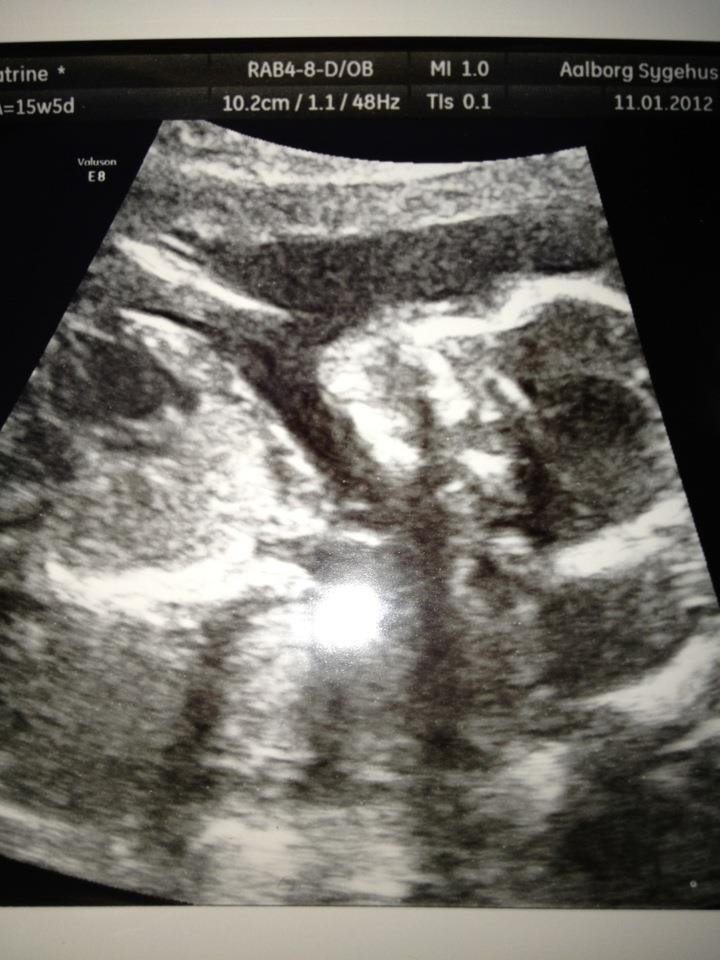

Scanningen gik bare rigtig fint og vores baby pige vokser, som hun skal - måler næsten 16 cm

Lægen sagde, at alt så normalt ud og at der er noget i hjernen, som skal være der før hjernebjælken kan være der (den som vores datter mangler), så det var bare rigtig godt

I får lige et par billeder med af vores dejlige Prinsesse